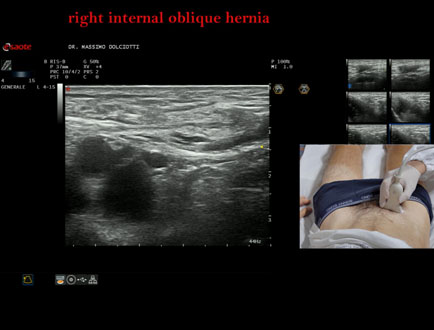

Data inserimento: 18/09/2025

Ecografia del: 11/09/2025

Strumento: Esaote MyLab Eight

Sonda: Lineare Multifrequenza 4-15 MHz

Età Paziente: M 48 anni

Motivazione dell'esame:tumefazione inguine destro.

Commento all'esame: le immagini ed il video documentano la presenza di ernia inguinale obliqua interna destra riducibile, con individuazione dell'anello inguinale sottocutaneo, anello inguinale addominale e canale inguinale.

Conclusioni: ernia inguinale obliqua interna destra (right internal oblique inguinal hernia).

Presentazione: Dr. Massimo Dolciotti - Ancona